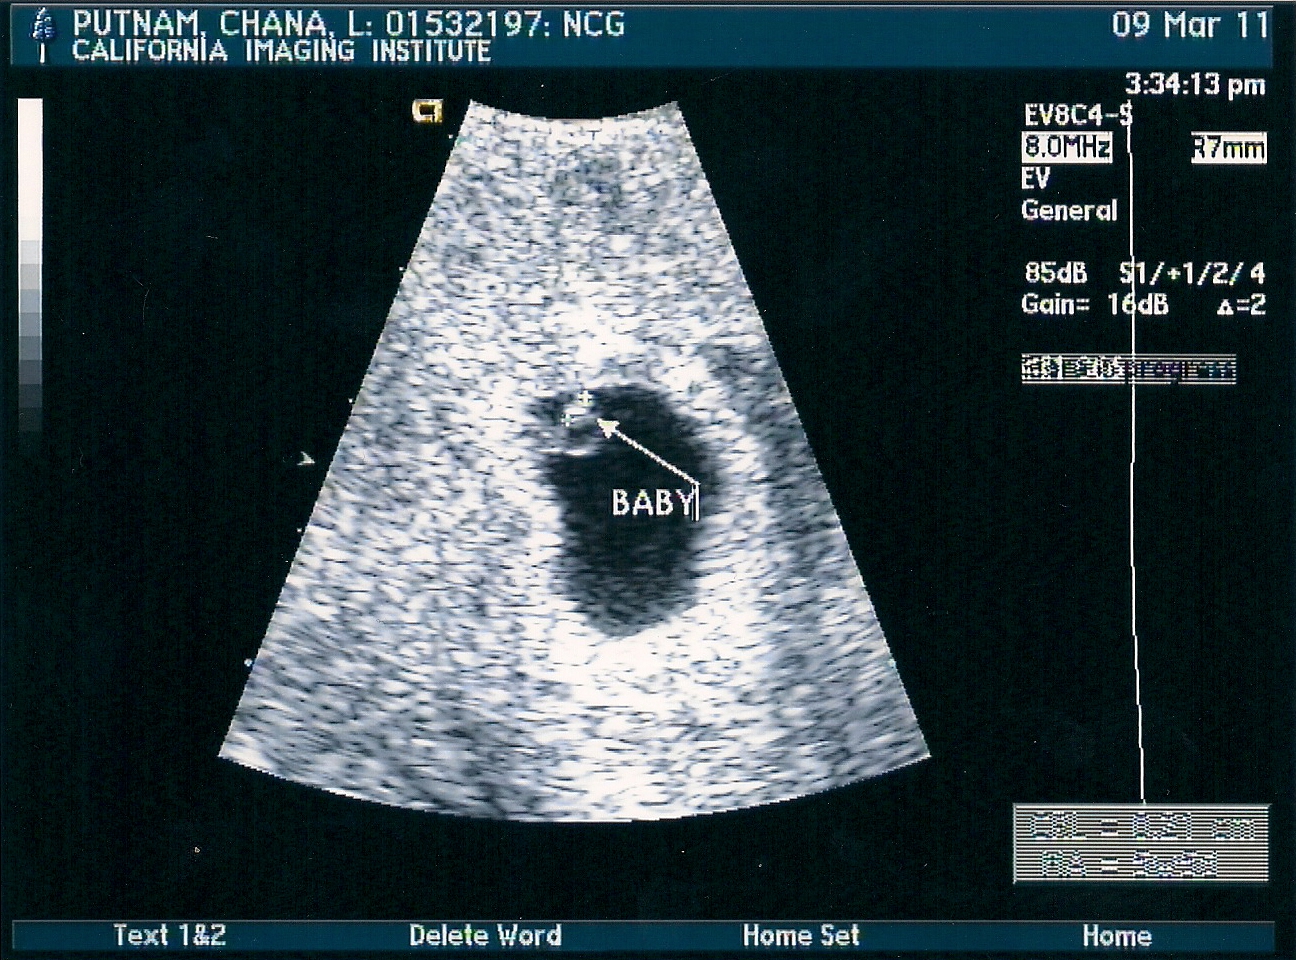

After our loss in December at 11 weeks we were ecstatic, but scared when we found out we were pregnant again only two months later. The fear mounted even more when I had a huge bleed and found out there was a blood clot next to the placenta. Needless to say that first trimester was a bit tense. Being in the second trimester is great though and we couldn't be more excited to welcome out little one ... or should I say little boy, into the world this coming fall.

We found out that we were most likely going to have a boy at our ultrasound at 12 weeks. Not wanting to get our hopes up of a boy we kept the sex a secret till our next ultrasound at 16 weeks. He's definitely a boy! Not only a boy, but a healthy boy and the blood clot is gone. All tests came back clear. More excitement came around the 16 week mark as well. I had just started feeling the flutters of our little one inside of me. That's always the best part of pregnancy and I miss it each time after birth.